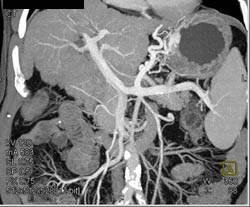

Cirrhosis With Varices